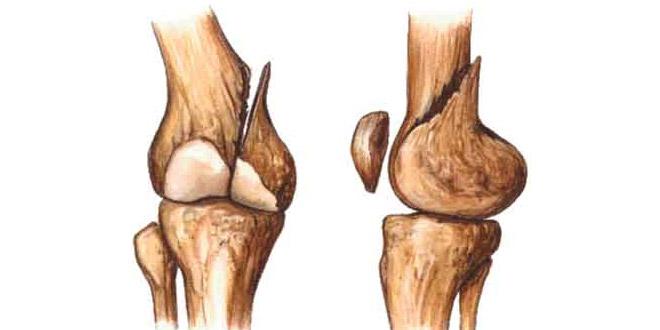

La salud de los huesos es un factor importante en tu vida, independientemente de la edad que tengas. Las medidas preventivas se deben tomar para asegurar que sus huesos sean fuertes y estén bien nutridos.

La dieta juega un papel clave en la construcción y mejora de la densidad ósea y la fuerza. Esto puede ser un factor importante en la velocidad de tu curación y la sanación del hueso.

La Dra. Susana Brown publicó un articulo que destacaba la importancia de la proteína y la vitamina D en la velocidad de curación del las fracturas óseas. Además la leche tiene otras vitaminas que se necesitan para reparar los huesos rotos.

Muy buena información, pero quiero consultar algo, en mi caso tuve un accidente en moto, un vehículo me arrolló, gracias a dios no fue a tanta velocidad pero igual tuve fractura de tibia y peroné, me operaron el mismo día de el accidente debido a que el peroné se expuso, Y me hice una herida considerable en el talón con fractura del calcáneo la intervención quirúrgica fue muy buena la tibia quedo muy bien alineada, me colocaron unos fijadores o tutures ya tengo un mes y 15 días y no soporto los dolores y el adormecimiento en el pies, paso la noche casi que sin dormir… Agradecería un buen consejo. Muchas gracias!

Hola hace una semana tuve un accidente de tibia y perone, una moto me atropelló :/ mientras cruzaba la calle con mi skate, la cuestión es que quería saber, si era una fractura muy grave… Y tenía la duda si podía a volver a andar en skate, ya que requiero mucho de la pierna izquierda. La verdad la situación es muy incómoda porque me pusieron una tracción y no puedo moverme, encima la otra me operan.